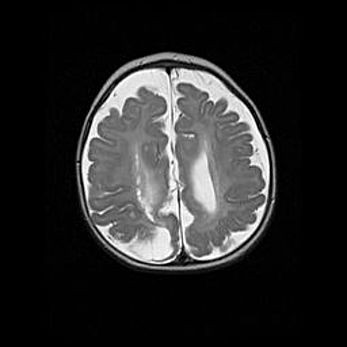

Лейкомаляция с кистозно-глиозной дегенерацией головного мозга.

Возраст: 2 месяца 25 дней

Вес: 6400 г

Окружность головы: 40 см

Срок гестации: 41 неделя

Лейкомаляцию относят к ишемически-гипоксическим повреждениям головного мозга, диагностируемым у новорожденных. При лейкомаляции в головном мозге обнаруживают очаги некроза, возникшие после тяжелой гипоксии и нарушения кровотока. В процессе морфогенеза очаги проходят три стадии: 1) развития некроза, 2) резорбции и 3) формирования глиозного рубца или кисты. Перивентрикулярная лейкомаляция (ПЛ) встречается примерно в 12% случаев среди новорожденных, обычно – у недоношенных детей, причем, частота ее зависит от массы, с которой младенец появился на свет. Наибольшее число малышей страдает лейкомаляцией, если масса при рождении 1500-2500 г.